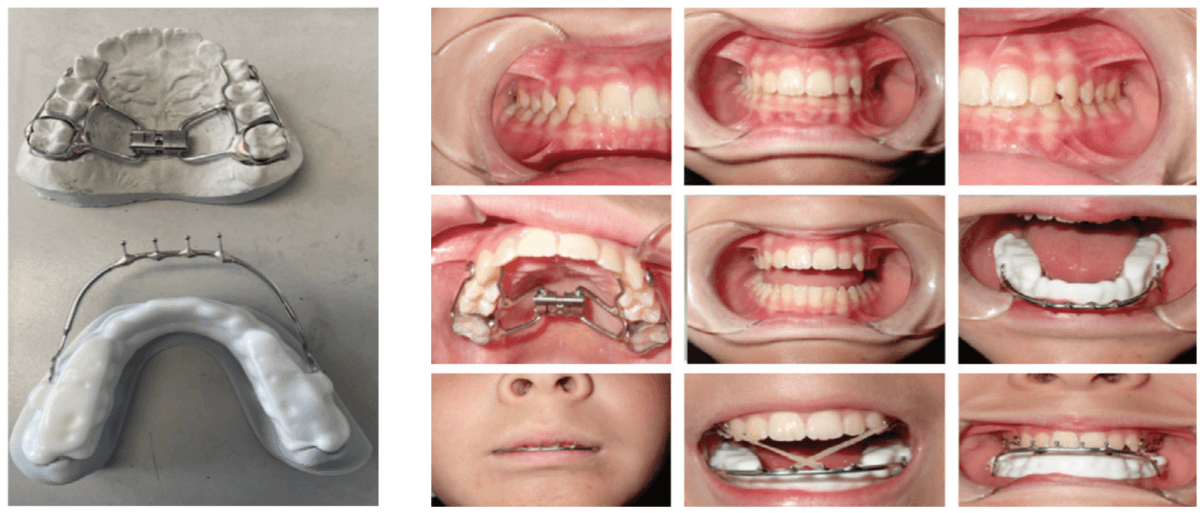

Decompressing the TM joints with a removable lower appliance at a physiologic position (sibilant phoneme registration/phonetic bite) has been shown to increase pharyngeal airway volume and decrease collapse. It also allows for stabilization of the TM joints, reducing pressure on the mandible without any pressure on the frontal bone.46,47 This Tandem Bow technique was explained in a previous case study titled, “Pediatric severe apnea/obesity/TMD/headache-Class III” in Orthodontic Practice US, May/June 2016, Volume 7, No. 3, pages 20-24. The 10-year-old patient who had been on CPAP for 5 years with an AHI of 118 was reduced to an AHI of 3 in 8 weeks and was able to discontinue her PAP therapy (Figure 8). Forward head posture corrections can be seen with decompression of the TM joints utilizing this technique (Figure 9). This technique is explained in Chapter 7 of Sleep Disorders in Pediatric Dentistry: Clinical Guide on Diagnosis and Management, edited by Dr. Edmund Liem, and published by Springer. Chapter 7 is authored by Dr. Edmund A. Lipskis, and titled, “Orthodontic and Dentofacial Orthopedic Treatment Strategies for Pediatric Sleep Disorders.” Advancing the entire maxilla is necessary to protract the palatine bones to increase the volume of the velopharynx (the narrowest part of the airway) (Figure 10).

The lower appliance that receives the Tandem Bow is to be worn 12 hours per day and only removed to eat if necessary. Most children should sleep for 10 hours, so the device can be worn during sleep, an hour before bed and an hour after waking. The force of the elastics, worn for 12 hours per day (mostly while sleeping), should have approximately 200g per side in mixed dentition and 250-300g per side in permanent dentition (Figure 11).

When used on mixed dentition, there will be a need to place extra buccal retention on the lower deciduous molars for the “C” clasps (Figures 12 and 13).